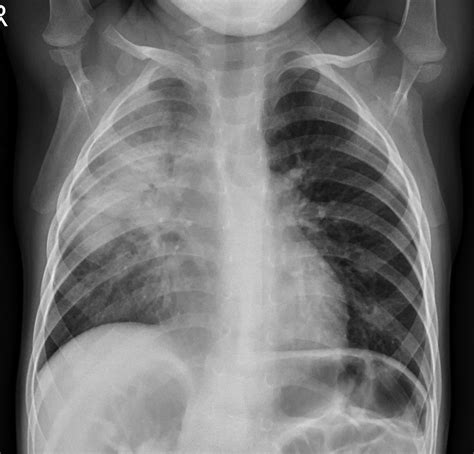

A Pneumonia X-ray is a medical imaging test that uses electromagnetic radiation to create pictures of the inside of your chest. When you have pneumonia, the air sacs (alveoli) in your lungs can become filled with fluid or pus. In an X-ray image, these filled air sacs appear as opaque, whitish patches or "opacities," which stand out against the dark, air-filled healthy lung tissue. This visual evidence is critical for doctors to distinguish pneumonia from other conditions like bronchitis or asthma.

When a radiologist reviews a Pneumonia X-ray, they are looking for specific indicators of disease. Healthy lungs on an X-ray typically appear black because they are filled with air, which does not block the X-ray beams. Conversely, infected tissue blocks these beams, leading to white areas on the film. These findings are often referred to in clinical reports as "infiltrates" or "consolidation."

Localized white patches (Consolidation) Indicative of active pneumonia infection

Cloudy shadows Possible interstitial inflammation or fluid